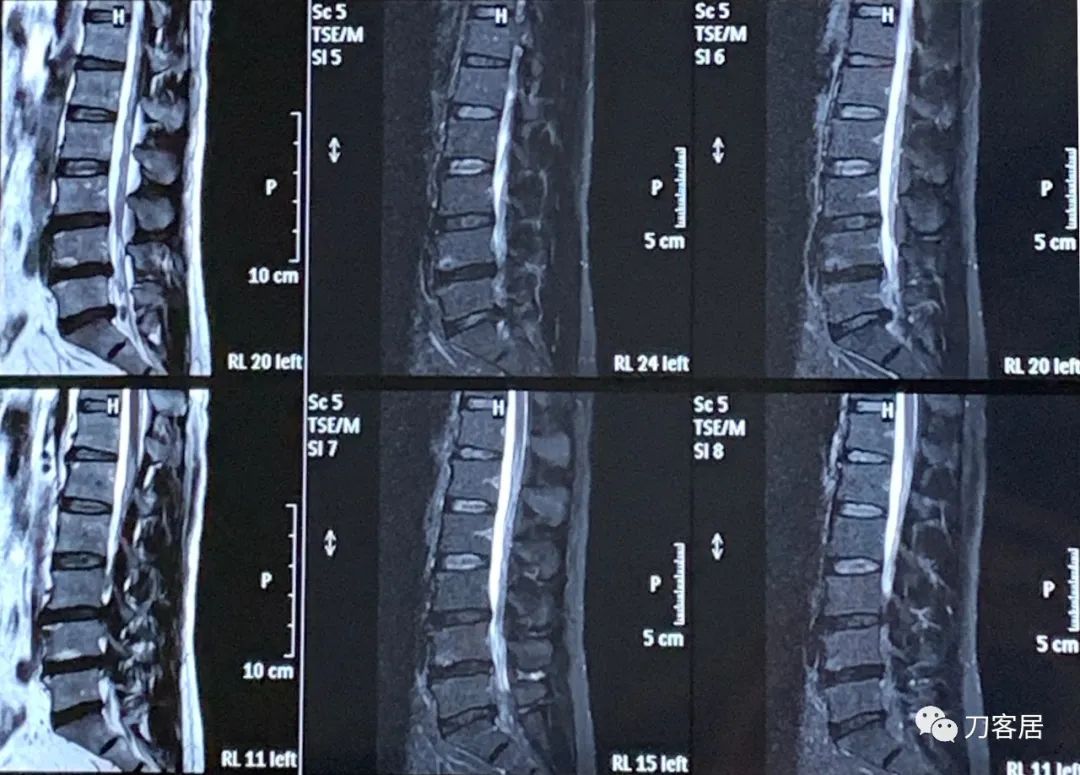

图4. 20220118宁夏医科大学总医院腰椎MRI01,矢状面扫描提示腰3-骶1椎间盘突出,不同层面显示不一致。

自带腰椎磁共振提示腰5骶1椎间盘突出,左旁侧型,腰3-5椎间盘突出,不严重。

诊断:腰5骶1椎间盘突出症(左旁侧型),腰3-5椎间盘突出。